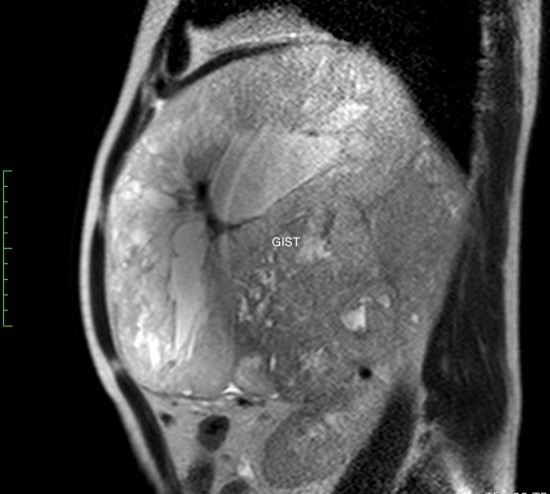

Гастроинтестинальная стромальная опухоль гигантских размеров, исходящая из большой кривизны желудка